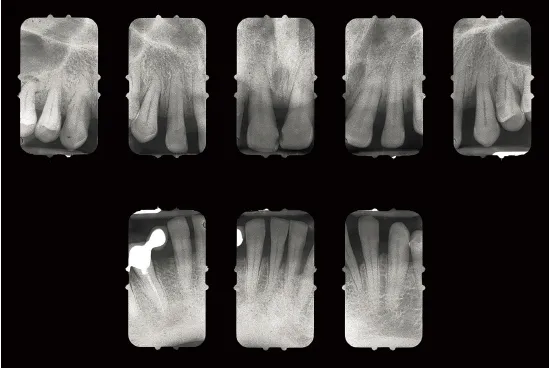

Fig 1-1a Aggressive periodontitis in a 40-year-old woman who is subject to stress and smokes one pack of cigarettes a day. The patient experienced an emotional shock 5 years earlier. A conventional treatment plan was initiated and included periodontal surgery throughout all quadrants. Professional maintenance (scaling and root planing) was carried out every 3 months, and the patient responded well.

Fig 1-1b Four years after treatment and maintenance therapy. Periodontal status has deteriorated in all areas. Observe the new attachment losses, dental migrations, and larger diastemata. It is clear that periodontal disease is not controlled. This patientās disease was refractory to conventional treatment. Specific risk factors in this patient were underestimated.